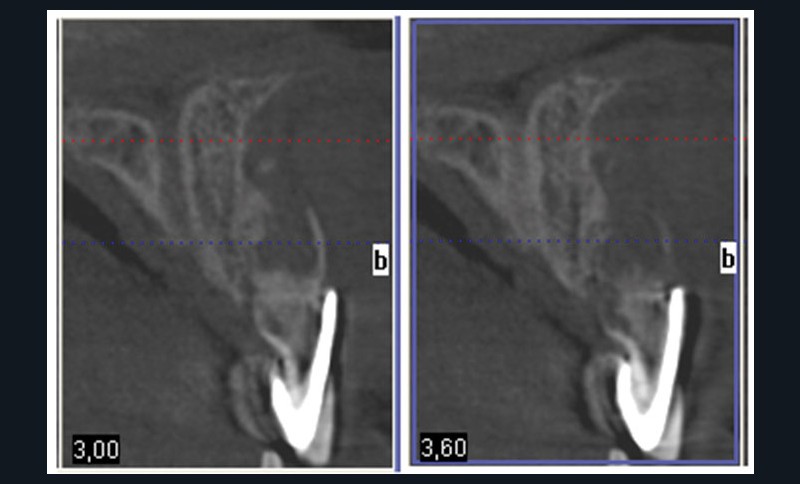

L’examen cone-beam permet de visualiser le volume osseux résiduel exploitable pour une implantation immédiate (fig. 5) malgré une perte de substance évidente.